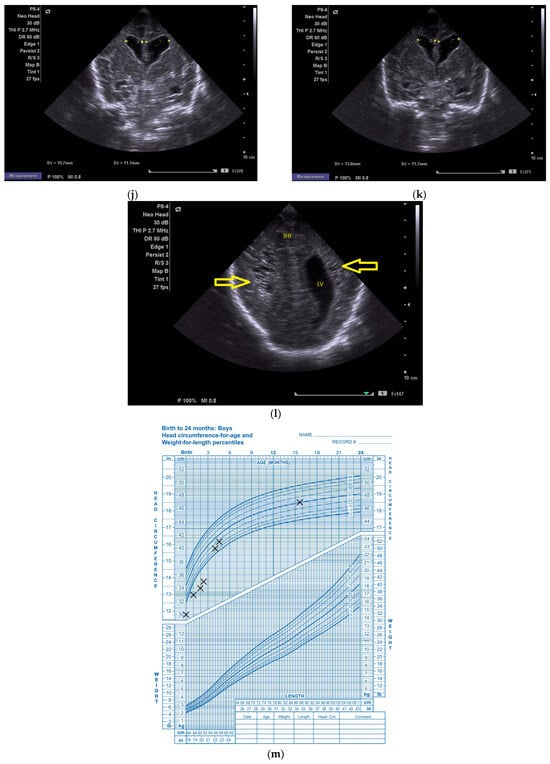

(a) Cranial ultrasound. Day one. Coronal view. D1 and D2—Levine index measurement. D3—cisterna magna measurement (personal image collection). (b) Cranial ultrasound. Day one. Coronal view. Lateral ventricle dilatation. LV—lateral ventricles. PC—plexus choroidus (personal image collection). (c) Cranial ultrasound. Day one. Right lateral ventricle. D1—thalamo-occipital distance measurement. Yellow arrow—parieto-occipital hyperechoic images (personal image collection). (d) Cranial ultrasound. Day one. Left lateral ventricle. D1—thalamo-occipital distance measurement. Yellow arrow—parieto-occipital hyperechoic images (personal image collection). (e) Day three. Cranial ultrasound. Coronal view. Ventricular asymmetry. D1 and D2—Levine index measurement. D3 and D4—anterior horn width measurement. Left ventricular enlargement (personal image collection). (f) Day three. Cranial ultrasound. Coronal view. Ventricular asymmetry (left ventricle larger than right ventricle). Yellow arrows—periventricular hyperechoic images are becoming more visible (personal image collection). (g) Day three. Cranial ultrasound. Coronal view. Linear probe. Ventricular asymmetry (left ventricle larger than right ventricle). LV—lateral ventricle (anterior horns). IHF—interhemispheric fissure. Yellow arrows—hyperechoic images in the thalamic-caudate groove (suggestive of a germinal matrix hemorrhage) (personal image collection). (h,i) Day 13. First LP. Cranial ultrasound. Coronal view. Up (before LP). D1 and D2—Levine index measurement. LV—lateral ventricles (anterior horns). IHF—interhemispheric fissure. Down (after LP). Dimensions of ventricles were reduced after LP. D1 and D2—anterior horn width. LV—lateral ventricles (anterior horns). OH—occipital horn (personal image collection). (j,k) Day 19. Second LP. Cranial ultrasound. Coronal view. Dimensions of ventricles were reduced after LP. Left (before LP). D1 and D2—Levine index measurement. Right (after LP). D1 and D2—Levine index measurement (personal image collection). (l) Day 39. Cranial ultrasound. Coronal view. Yellow arrows—periventricular cystic hyperechoic images—suggesting periventricular leukomalacia (cystic form) (personal image collection). (m) Head circumference-for-age. “X” symbols represent the measurements performed from birth and follow-up examinations. Initially, the head circumference was under the curve (personal image collection) [28].

After 72 h, the patient was extubated. The CUS showed bilateral IVH (grade III Volpe/Papile) (Figure 1e,f).

During the in-stay, two lumbar punctures (LP) were performed (Figure 1h–k).

In evolution, our patient presented bilateral ventricular dilatation and bilateral PVL (cystic form, grade III) (Figure 1l). The neurological assessment established eye contact and the infant could hold its head during the traction maneuver. The passive tone assessment showed the “scarf sign”, with the elbow at the midline bilaterally and a popliteal angle of 90°. The deep tendon reflexes (DTRs) were symmetrical.

Clinically, hypertonicity of the legs and axial muscles was present. At the one-year follow-up examination, the patient showed developmental delay and strabismus. At the three-year follow-up examination, cerebral palsy could be observed, which was bilateral and spastic with a predominance of the legs. The classification according to the Gross Motor Function Classification System (GMFCS) was grade III.